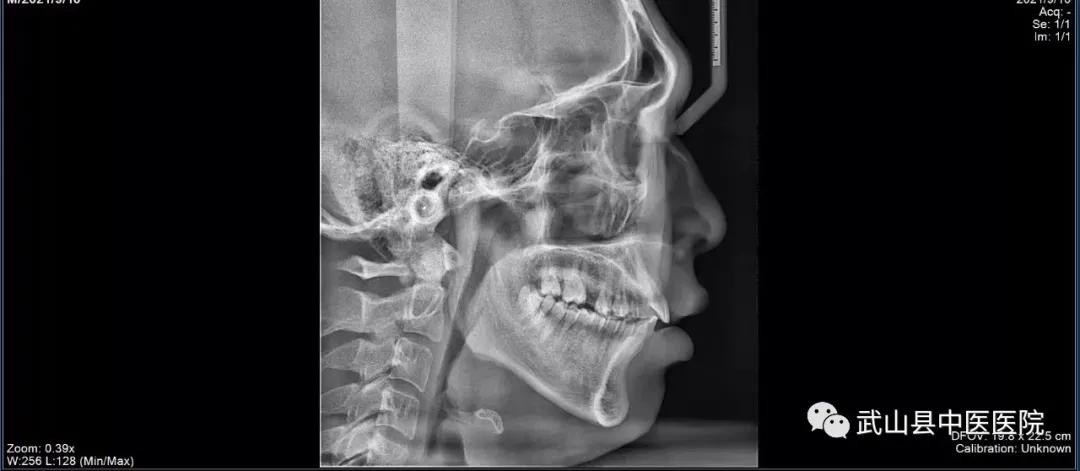

为了更好地服务全县人民,满足人民群众口腔健康需求,实现“口腔健康、全身健康”的目的。武山县中医医院口腔科引进集全景、头颅、CBCT功能于一体的三合一口腔CBCT设备,该设备可以清晰地显示牙齿颌骨的细微结构及牙体牙髓牙周组织,进一步增强了县中医医院口腔科诊疗水平 。

CBCT的应用领域非常广泛,可以运用于口腔学科的各个细分领域,包括种植、正畸、口腔颌面外科、牙体牙髓病、牙周病、颞下颌关节疾病等细分领域。三合一口腔CBCT具有自动咬合定位、三点头颅定位系统、主动侦测颌弓形态、快速投照功能,是更加精细化、专业化的诊断工具,适用于颌骨骨折、骨质破坏(肿瘤、囊肿、骨髓炎、骨结核)、牙齿损伤(牙折、牙脱位)、阻生牙拔除前的治疗计划,为检查修复的牙体邻面及旧修复体周围牙体组织有无龋坏、牙周组织的损害、牙槽骨吸收情况、根管治疗情况、根尖病变情况、牙体发育异常的诊断提供依据。